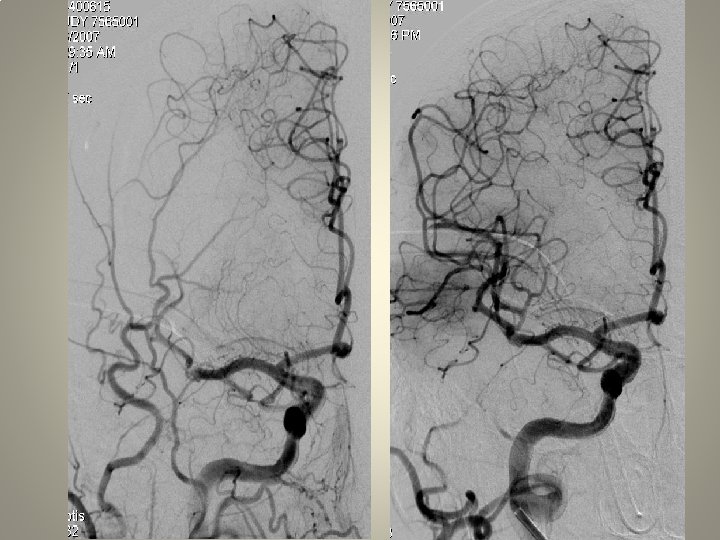

Neden stent? TANDEM lezyon

Neden stent? Distal emboli koruma

Neden stent? Eş zmanlı komplikasyon idaresi